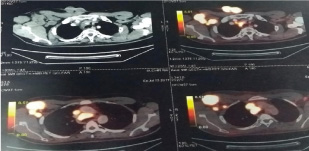

Then, the patient came back after 1.5 years in June, 2017 with a bleeding, ulcerated nodular growth over anterior chest wall and swelling over right anterior axillary fold [Table/Fig-4]. A biopsy was done which showed metastatic nasopharyngeal carcinoma. Finally, a Positron Emission Tomography-Computed Tomography (PET-CT) was done which showed a heterogeneously enhancing FDG avid exophytic cutaneous and sub cutaneous soft tissue lesions in right anterior chest wall and multiple FDG avid heterogeneously enhancing enlarged right axillary and subpectoral nodes. Few small mild FDG avid lymph nodes in left axillary and mediastinal nodes were also seen [Table/Fig-5].

PET-CT Scan film showing cutaneous, right axillary and mediastinal metastses.